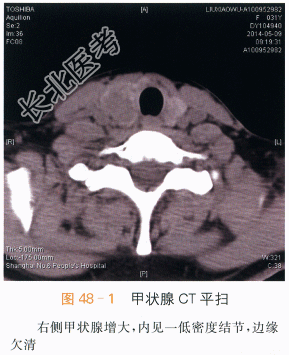

影像学资料如图48-1~图48-4所示。

本案例CT扫描见右侧甲状腺增大,结节与正常甲状腺分界不清,呈低密度,见沙砾样钙化(见图48-1),增强后呈低度强化,甲状腺包膜不完整,(见图48-2~图48-4),结合超声检查,考虑甲状腺癌。